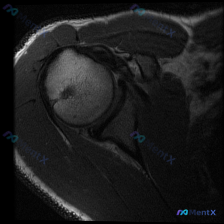

最近看到一个肩部MRI病例,资料里只有T1序列冠状位影像。影像分析显示:肱骨头、肩胛盂形态正常,冈上肌腱走行连续无撕裂,上方盂唇呈三角形低信号、轮廓规则,未见明显的信号异常或撕裂征象。 虽然影像没找到盂唇的结构性病变,但患者很可能有持续性肩痛症状(不然也不会做MRI)。大家第一眼看到这种情况,会先往...